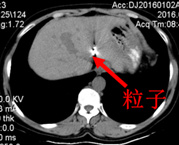

术后CT(9月)图像:

2015-10-26行CT定位下左肝占位碘125放射粒子植入术。